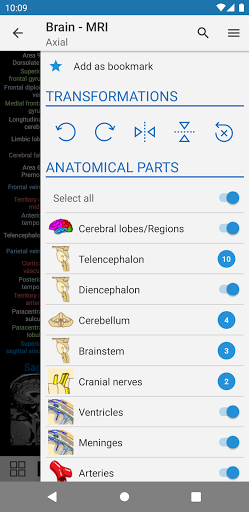

- يمكنك الآن إخفاء الهياكل واحداً تلو الآخر (زر جديد داخل نافذة الوصف المنبثقة) وعرضها مرة أخرى في القائمة الصحيحة